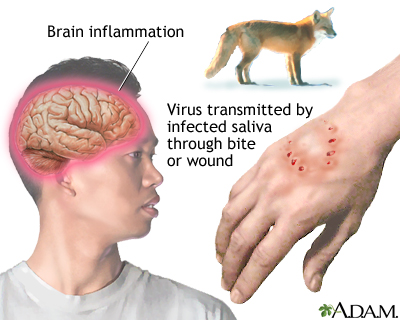

Many other vaccines are available, including vaccines for:

- Rabies

These vaccines are not routinely given to the general population. They are only recommended to people who are at risk of exposure to the specific germ. For more information about these vaccines, visit the CDC website -- www.cdc.gov/vaccines/vpd/vaccines-diseases.html.

People who are traveling to countries where certain infectious diseases are common should seek consultation in a travel clinic or check with the Centers for Disease Control and Prevention (www.cdc.gov/travel) for up-to-date information on immunization requirements for their destinations.

- Some countries require vaccinations against specific diseases such as yellow fever, meningitis, typhoid, cholera, Japanese encephalitis, and rabies under certain circumstances.